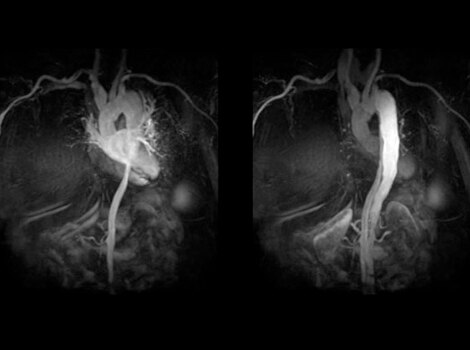

SIGNA Works CV 成像与分析工具

通过一个自由呼吸,心脏 MR 即可评估出心脏形态、功能、血流、组织活力和冠状动脉解剖结构,而无电离辐射危害。 了解更多信息

无创心脏 MR 用于评估心脏形态、功能、血流、组织活力和冠状动脉解剖结构,而无电离辐射危害。了解更多信息

SIGNA™ Works CV 成像与分析工具